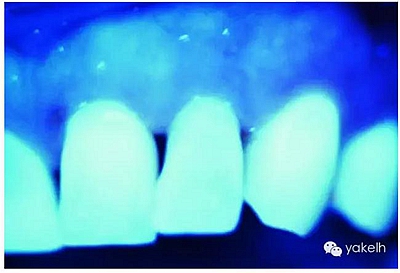

天然牙暴露在紫外線光下顯示熒光,通常是白色淡藍色的色調(藍白色)[13,22]。由于有機物的存在,以及大量有機物色素對紫外線光譜的感光性,牙本質是產生熒光的主體,比牙釉質的熒光更強烈。

圖2.30,圖2.31通過紫外線光照下的天然牙齒,顯示牙齒的熒光性。